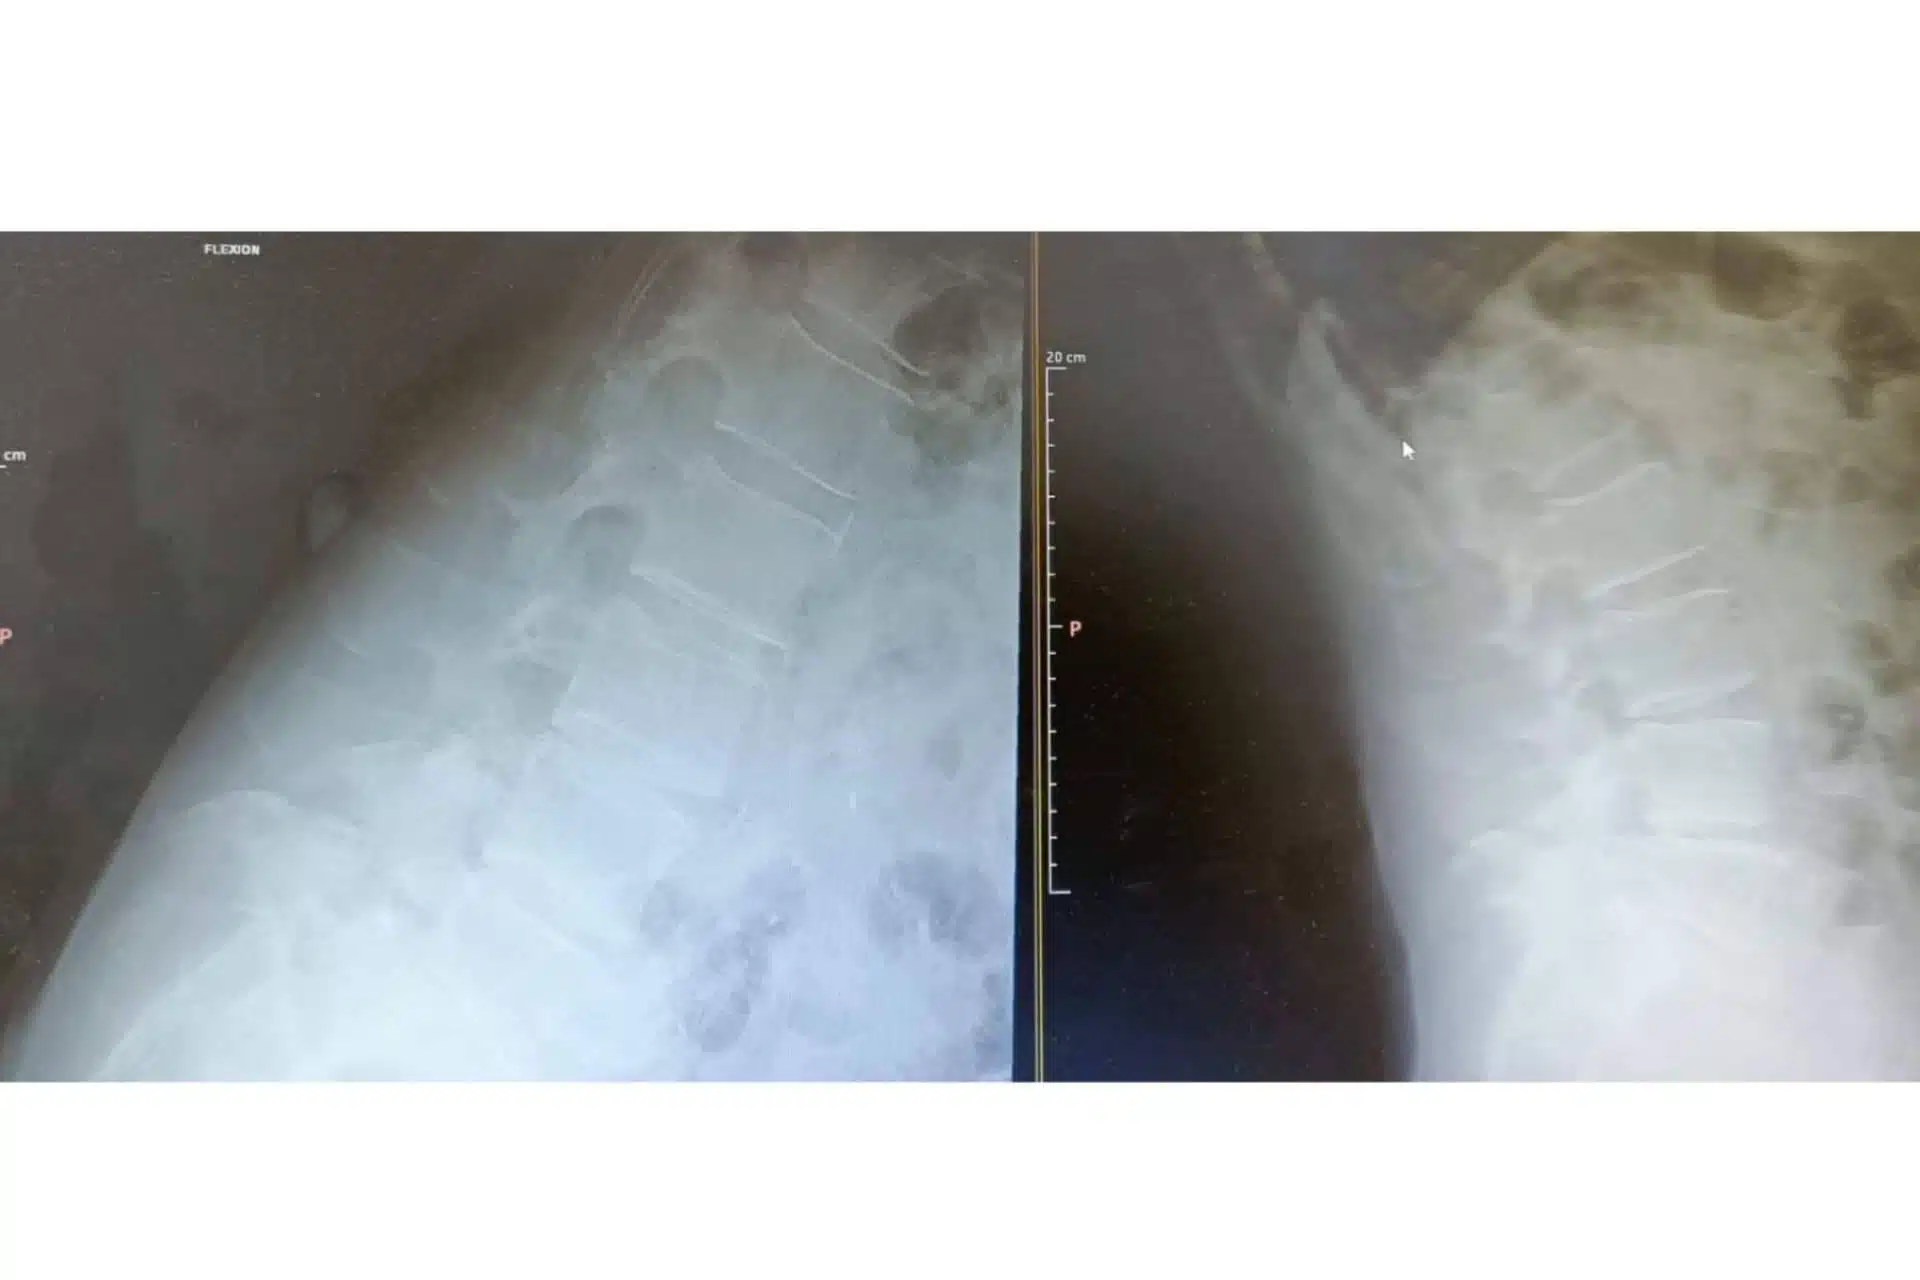

Su ejecución, por otra parte, se lleva a cabo en un quirófano bajo sedación y anestesia local, para lo cual es necesario hacer un estudio preparatorio con el anestesista en días previos. El procedimiento suele durar entre 30 y 50 minutos, durante los cuales, se realiza la extracción de los fragmentos del disco que provocan la dolencia. Para ello, se utiliza un fluoroscopio, que permite localizar con precisión la zona a intervenir y, así, evitar cualquier error o intervención en zonas que no se ven afectadas por la hernia.